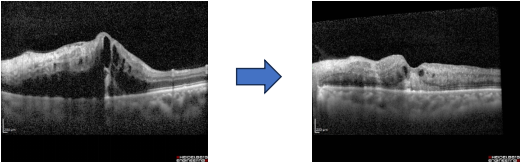

图片2.png患者术前的光学相干断层扫描(OCT)结果,可见黄斑水肿明显,术后水肿减轻。

玉溪市中山医院眼科副主任李琼波医生收治了该患者,在玉溪市人民医院曾颖副主任医师的指导下,制定详细诊疗方案,并在手术室顺利完成医院首例玻璃体腔注药术。术后第二天即观察到患者黄斑区水肿明显减轻,视力较前有效提升。